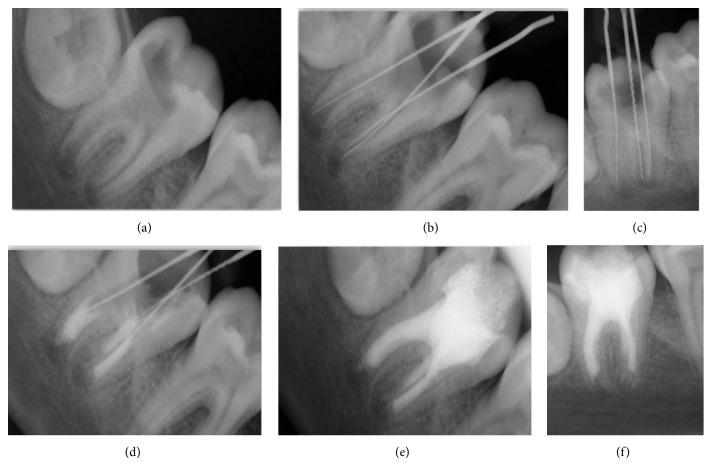

Single visit apexification using mineral trioxide aggregate (MTA) is a new boon in effective management of nonvital tooth with an open apex which has steadily gained popularity with clinicians; also it shortens the treatment period and improves patient compliance. Importance of this approach lies in expedient cleaning and shaping of the root canal system, followed by its apical seal with MTA. There are several case reports available describing the use of MTA as an apexification agent in incisors and premolar, but presented cases are the unique case reports demonstrating successful apexification procedure using MTA in young permanent mandibular molars. After eight-month follow-up, teeth were without any abnormal clinical symptoms; rather there were radiographic resolution of the periapical lesion and induction of root end closure with new hard tissue formation over MTA.

使用三氧化矿物凝聚体(MTA)进行单次就诊根尖诱导成形术是治疗根尖开放的无髓牙的一项新的有效方法,在临床医生中越来越受欢迎;它还缩短了治疗周期,提高了患者的依从性。这种方法的重要性在于对根管系统进行便捷的清理和预备,随后用MTA进行根尖封闭。有几篇病例报告描述了MTA作为切牙和前磨牙根尖诱导成形剂的应用,但本文所展示的病例是独特的病例报告,展示了在年轻恒牙下颌磨牙中使用MTA成功进行根尖诱导成形术的过程。经过八个月的随访,牙齿没有任何异常临床症状;相反,根尖周病变在影像学上得到了消退,并且在MTA上方有新的硬组织形成,诱导了根尖封闭。